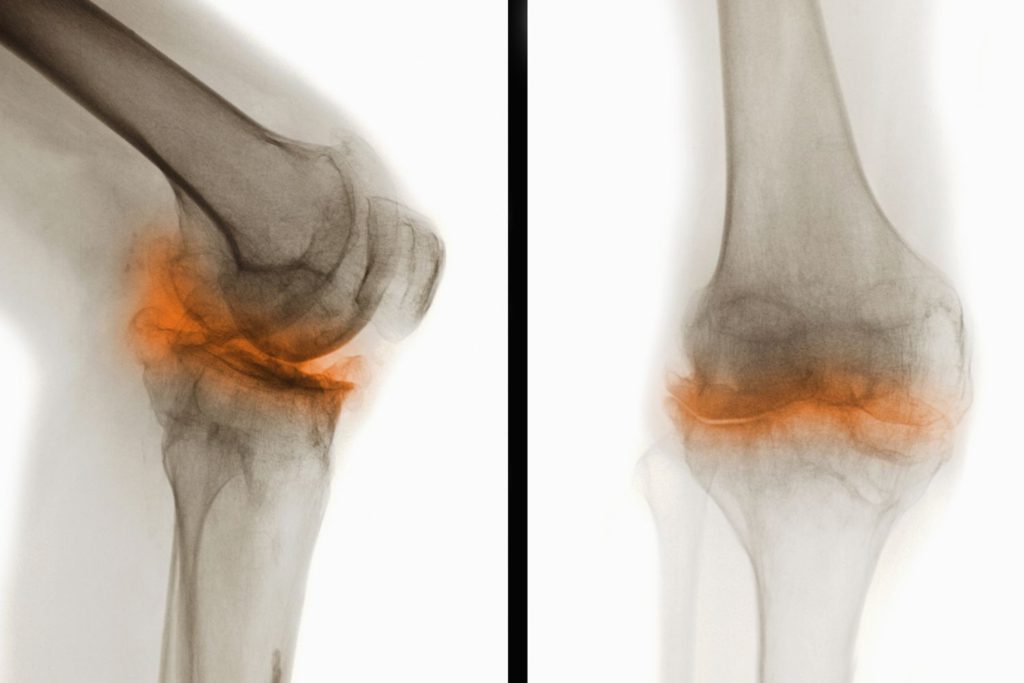

Деформирующий остеоатроз

Наиболее распространенная болезнь коленных суставов. По статистике, каждый третий человек, имеющий проблемы с коленями, страдает именно от этой патологии. Деформирующий остеоатроз обычно развивается в возрасте более 40 лет. Чаще всего страдают женщины, спортсмены, лица с избыточной массой тела и люди, выполняющие тяжелую физическую работу.

Деформирующий гонартроз – это хроническое дегенеративно-дистрофическое заболевание, ведущее к постепенному разрушению внутрисуставных хрящей. При отсутствии адекватной терапии патология ведет к прогрессирующему снижению работоспособности и даже инвалидности. Но правильное своевременное лечение не позволяет избавиться от остеоартроза, а всего лишь замедляет его развитие.

На начальных стадиях симптомы этой болезни коленного сустава слабо выражены или вовсе отсутствуют. Со временем больного начинают беспокоить ноющие боли в суставе, возникающие после резкого вставания со стула, во время ходьбы, при подъеме по лестнице. Вскоре заболевание приводит к выраженному нарушению подвижности колена.